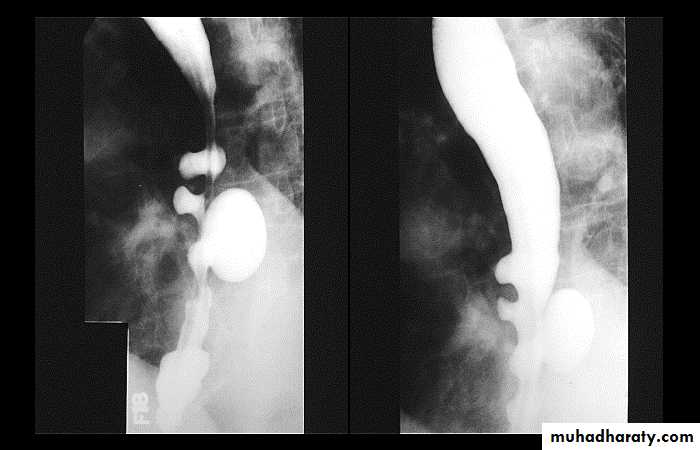

Sliding herniaOn the left initially, GE junction is below the esophageal hiatus. Later, stomach protrudes through hiatus

Para esophageal hernia

GIT

On the far left gas filled gastric funds (asterisk) protrudes through hiatus but GE junction (arrow) is below diaphragm